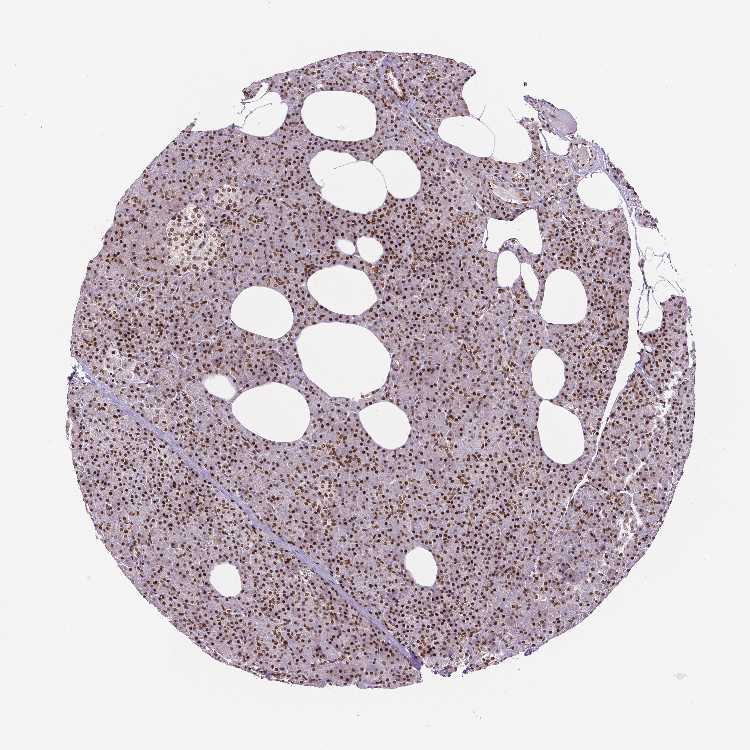

TISSUE PRIMARY DATA PANCREAS Show tissue menu

PANCREAS - Antibody stainingi

Antibody staining in the annotated cell types in the current human tissue is reported as not detected, low, medium, or high, based on conventional immunohistochemistry profiling in selected tissues. This score is based on the combination of the staining intensity and fraction of stained cells.

Each image is clickable and will lead to virtual microscopy that enables deeper exploration of all samples and also displays staining intensity scores, fraction scores and subcellular localization as well as patient and tissue information for each sample.

Antibody HPA004122Antibody CAB062550Antibody CAB068181Antibody CAB068182

Exocrine glandular cells HighMediumHighHigh

Pancreatic endocrine cells -LowMediumMedium